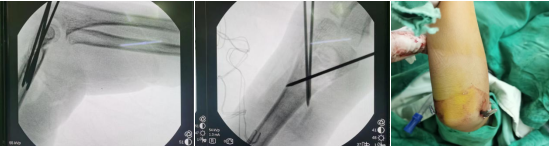

骨外科一區(qū)副主任醫(yī)師李金盤在手術(shù)室透視機下急診為玲玲行肱骨髁上骨折外側(cè)小切口克氏針內(nèi)固定術(shù),將患兒創(chuàng)傷和術(shù)中風險降到最低,手術(shù)順利。